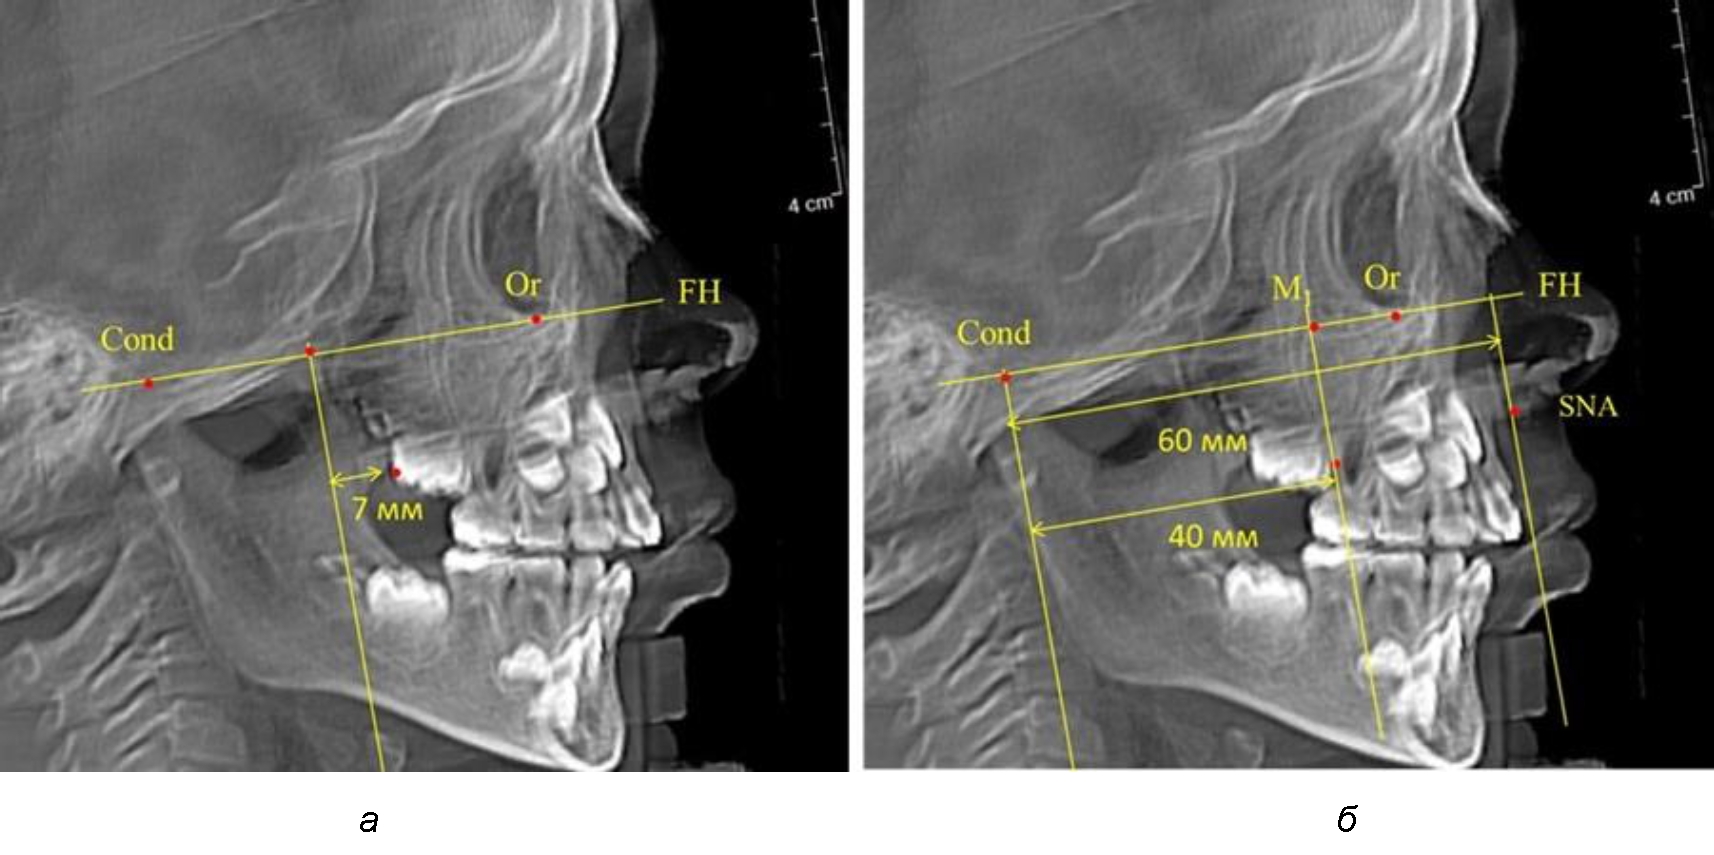

Второй частью исследования был анализ положения первых постоянных моляров в различные периоды сменного прикуса. На телерентгенограммах детей периода прикуса молочных зубов дистальная поверхность зачатка первого постоянного моляра отстояла от крыловидной вертикали на величину, составляющую около 7 мм, что было близким по значению к данным R. E. McDonald. Сагиттальный размер гантического отдела составлял около 60 мм, а его отношение к кондилярно-молярной глубине – 1,5 (рис. 4).

Рис. 4. Особенности положения первых моляров по R. E. McDonald (а) и по предложенному методу (б) у ребенка 4 лет